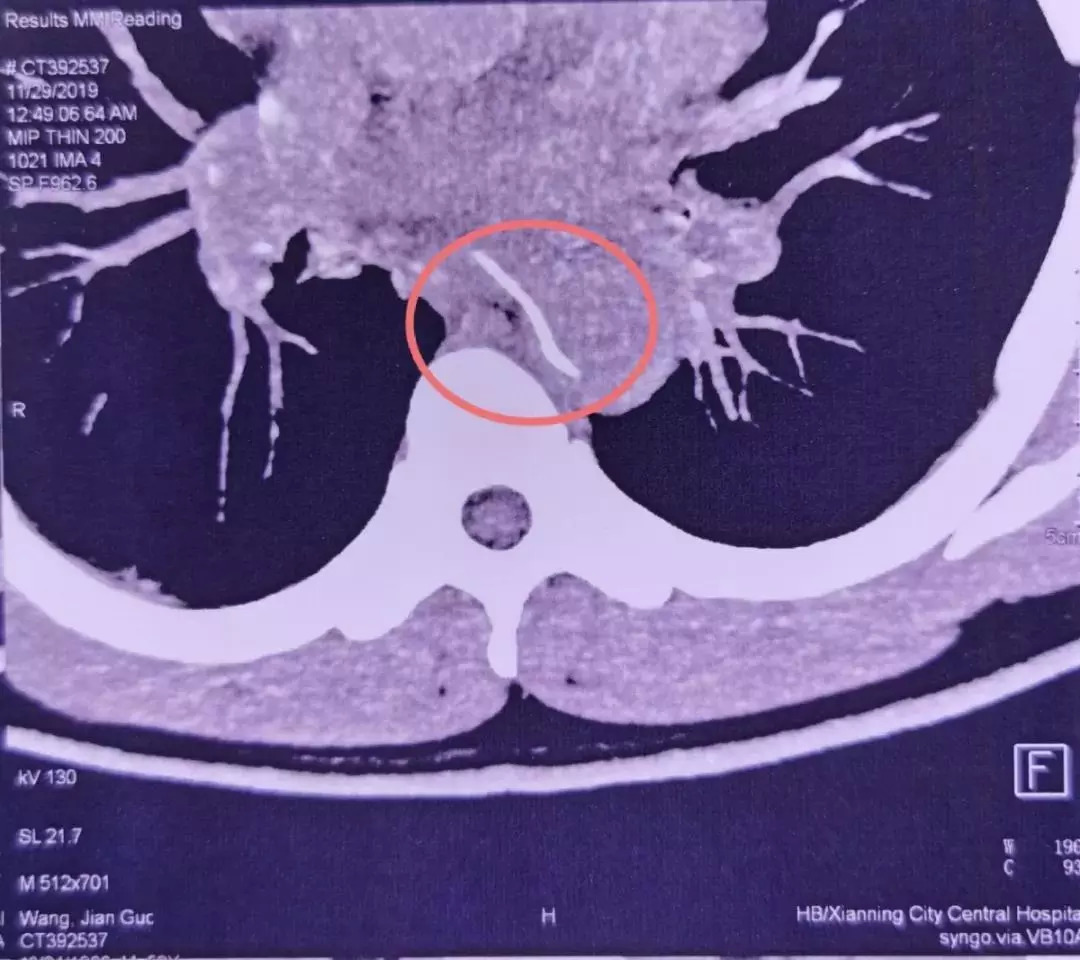

28 号这天,他突然感觉到剧烈胸痛,于是赶忙到咸宁当地的医院检查。医生很快安排了 CTA(CT 血管造影)。结果发现,一根鱼刺样的异物卡在了老林的食道内,并且已经刺穿了食道壁,扎进了胸主动脉。

图片来源:武汉大学人民医院

第二天一大早,重症医学科的魏捷听值班医生报告了这个病例。她看到检查结果后,发现鱼刺像一把「弯刀」架在食道和主动脉之间,就像主动脉上突兀地长出了一根刺。